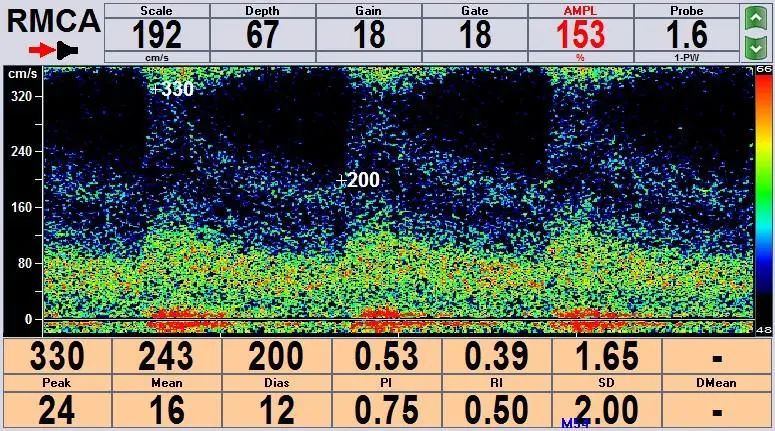

患者,男,52岁,发作性左侧肢体活动不灵就诊。头MRI提示未见异常病灶。TCD提示右侧大脑中动脉重度狭窄。通过血管超声的筛查,找到了临床事件的“始作俑者”-责任血管。